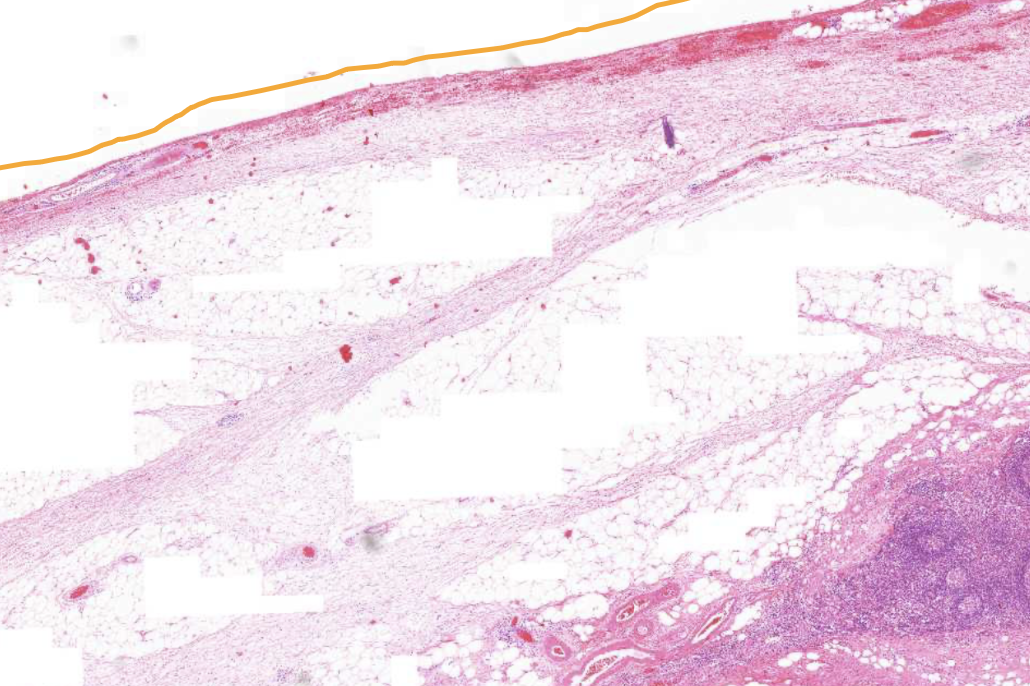

Poorly differentiated colon adenocarcinoma - Serosa

The serosa is facing the peritoneal cavity

Adipose tissue on the other side of the muscularis externa

Poorly differentiated colon adenocarcinoma - Serial surface

A bit damaged during surgery

No apparent visible mesothelium